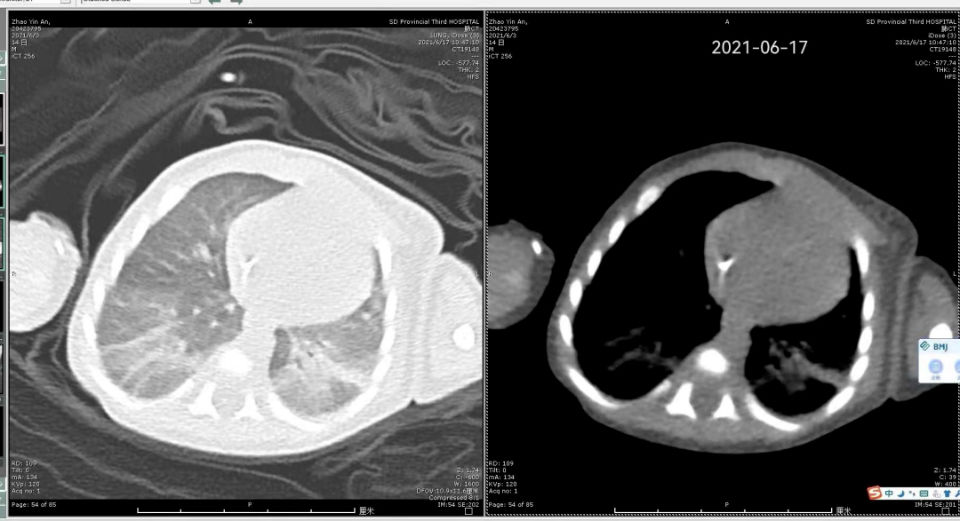

【 危重症|32天早产危重症患儿实施纤维支气管镜检查治疗】患儿病情危重,呼吸困难、呻吟、发绀,山东省立三院新生儿科医疗团队立即给予气管插管、无创呼吸机辅助通气、抗感染等积极抢救治疗。但患儿肺部炎症好转不明显,撤机、脱氧困难。山东省立三院儿科主任马燕紧急组织医疗团队开展疑难病例讨论,考虑患儿肺部炎症经抗感染治疗效果欠佳,需明确致病菌指导治疗,并进一步了解有无先天性气道发育畸形等情况,为患儿实施纤维支气管镜检查及肺泡灌洗术是最佳选择。

儿科王祥宇医生在新生儿病房为患儿实施了床边纤维支气管镜检查及肺泡灌洗术。术中采用局部麻醉下经鼻孔进镜,仔细探查患儿气管、支气管等情况。左肺下叶基底段可见较多粘痰样分泌物,管腔内可见粘痰样分泌物堵塞,通气不佳,给予分次灌洗,并收集灌洗液进行病原学检测。术中密切监测患儿生命体征,手术过程顺利,患儿生命体征平稳,无不良反应。大家都为这个幼小而强大的生命松了口气。